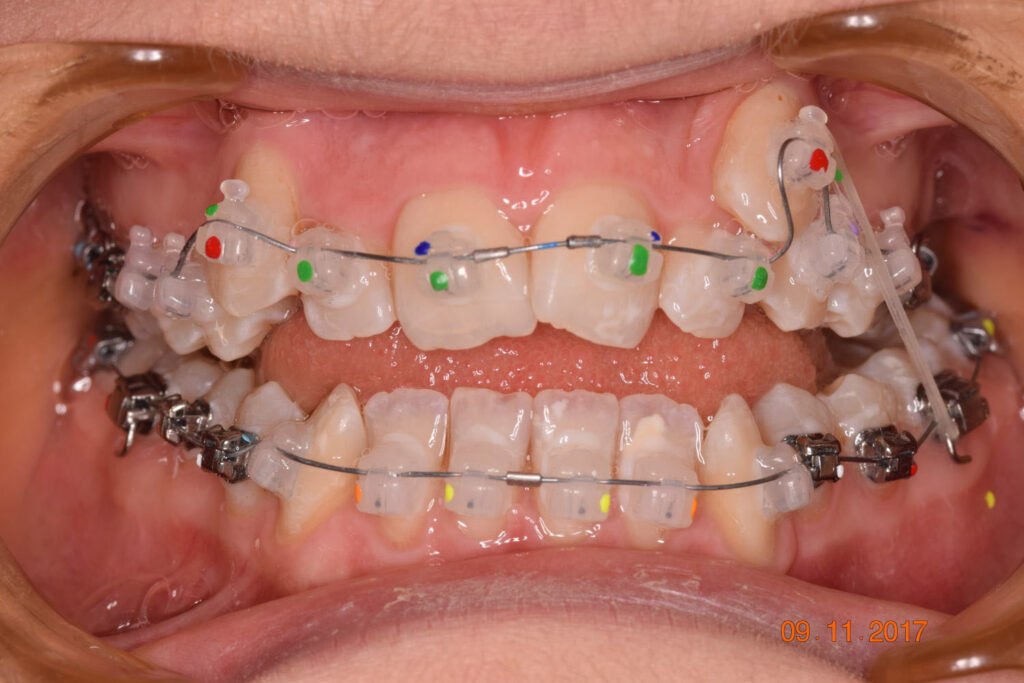

The treatment began in 2017. Given the patient’s preference for less visible brackets, Damon Clear brackets were selected. High torque upper cuspids and low torque upper incisors were chosen to offer the best torque control for upper arch development. For the lower arch, there were no alternative bracket configurations available. Bite turbos were applied to the upper second molars.

This case posed challenges in all three spatial dimensions, compounded by significant crowding. The patient was highly compliant and maintained excellent oral hygiene throughout the 5.5 years of treatment, which required more than 30 clinical appointments.

This case was a learning moment for Dr. Coca, reshaping his understanding of low-force, low-friction orthodontics (also known as Damon Philosophy) and highlighting the power of myofunctional therapy in achieving optimal treatment outcomes.